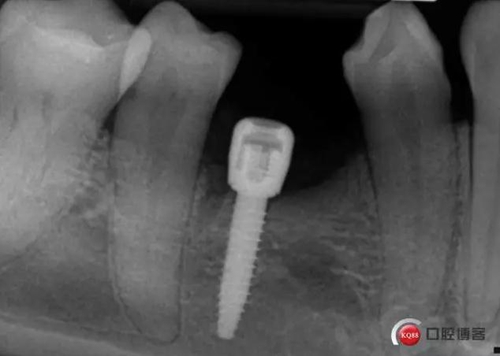

偏遠中植入。 術后病人恢復良好, 無感覺異常。

三個月后上基臺